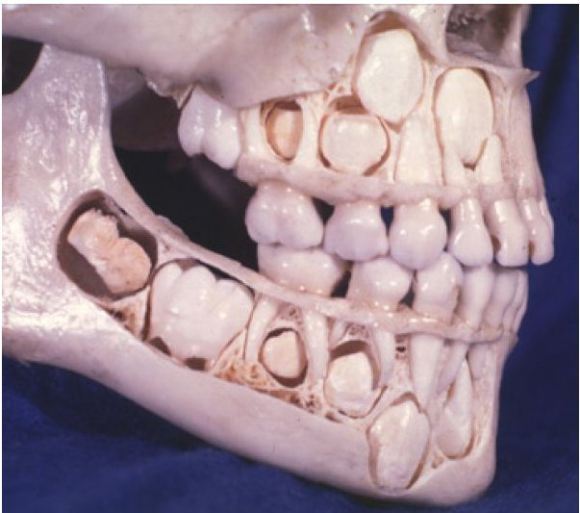

23: <丶`∀´>(´・ω・`)(`ハ´ )さん@\(^o^)/ 2016/07/17(日) 08:01:03.57 ID:NzwO67H4.net

やっぱ、こうゆう構造なんだね。

キモ!!

右上の糸切り歯の場所に乳歯がいすわっていて

中の歯の種みたいな奴が埋まっていて目の方向に向かって生え始めたんだな

おたまじゃくしと同じで

歯ってのは頭ができて、足が生えてくると思ってくれ。

歯の頭が乳歯に邪魔されて向きが変わってしまったのが原因だ

親知らずだと たま~にあるんだけどさ